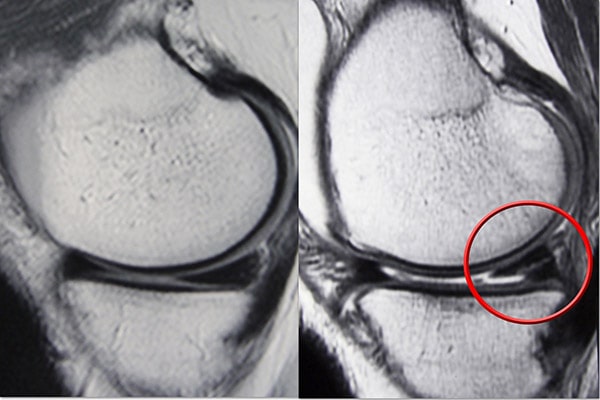

磁共振成像 (MRI) 扫描。 MRI 扫描可评估膝关节的软组织,包括半月板、软骨、肌腱和韧带。